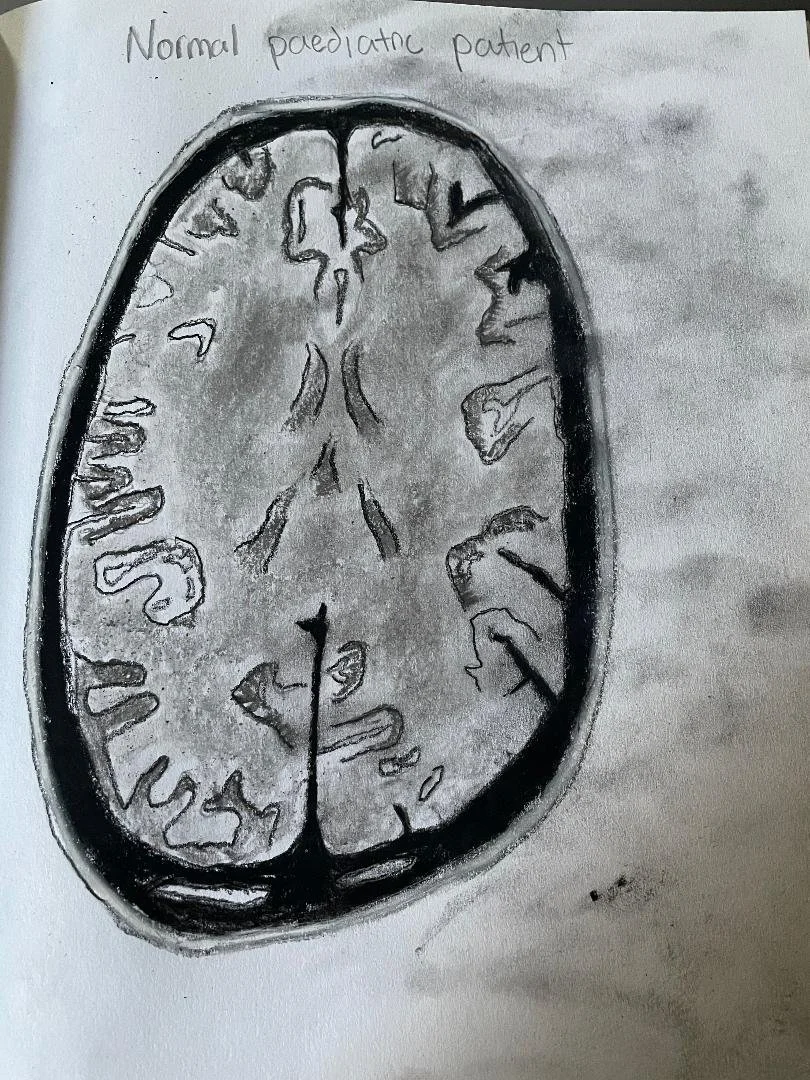

Normal MRI of the brain - 9-year-old